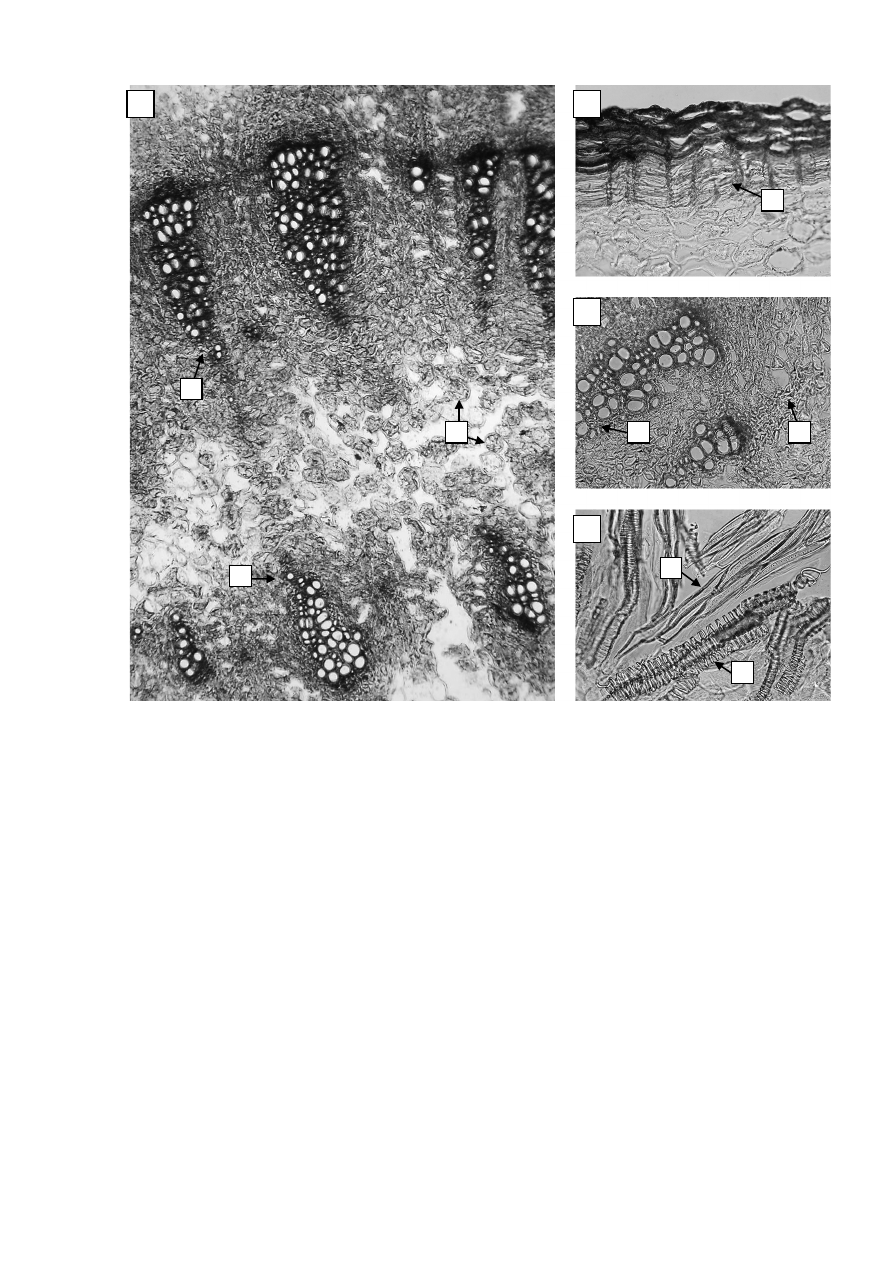

Рисунок

1 –

Родиолырозовой

корневища и корни

фрагмент поперечного среза корневища: а

–

сосудисто

-

волокнистые

пучки первого кольца, б

волокнистые пучки второго кольца,

в

клетки паренхимы (

40×); 2 –

фрагмент поперечного среза корневища:

а

многослойная пробка (

200×); 3 –

фрагмент поперечного среза корневища,

волокнистые пучки: а

сосуды ксилемы, б

флоэма (

200×);

4 – «

давленый

»

препарат: а

склеренхимные волокна с утолщенными

пористыми стенками, б

фрагменты спиральных и лестничных сосудов

(200×).